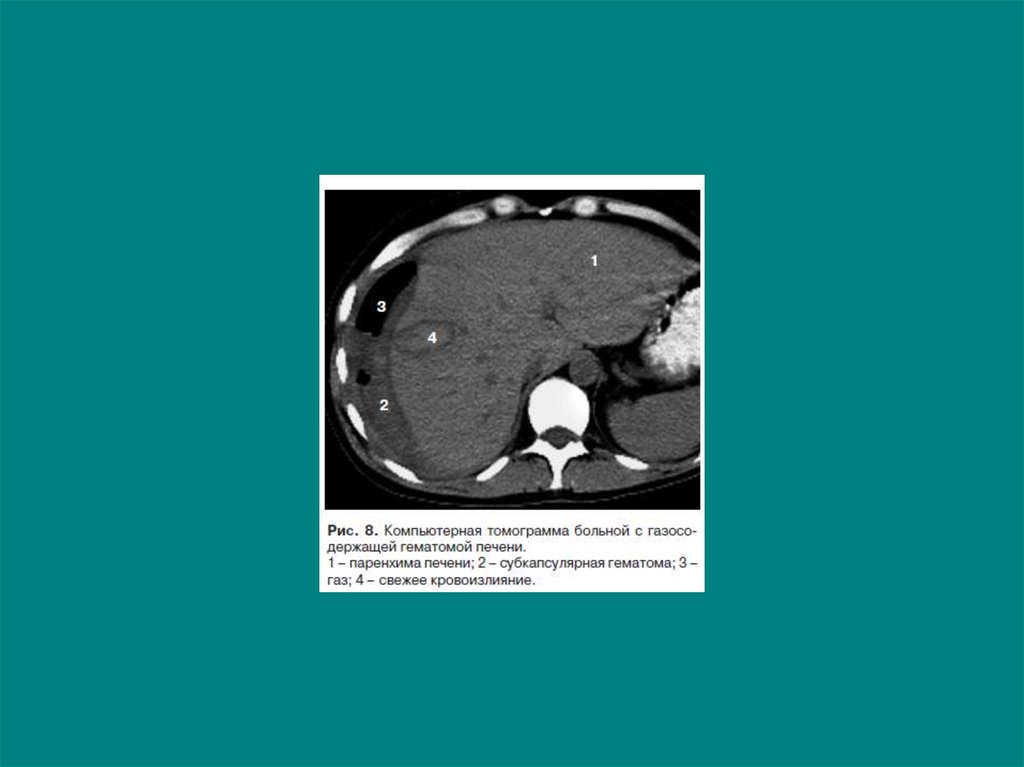

6. Травма печени

Подкапсульная гематома печени (n=23)

2 сутки

9 сутки

8. Травма печени

Исследования в динамике (n=32)